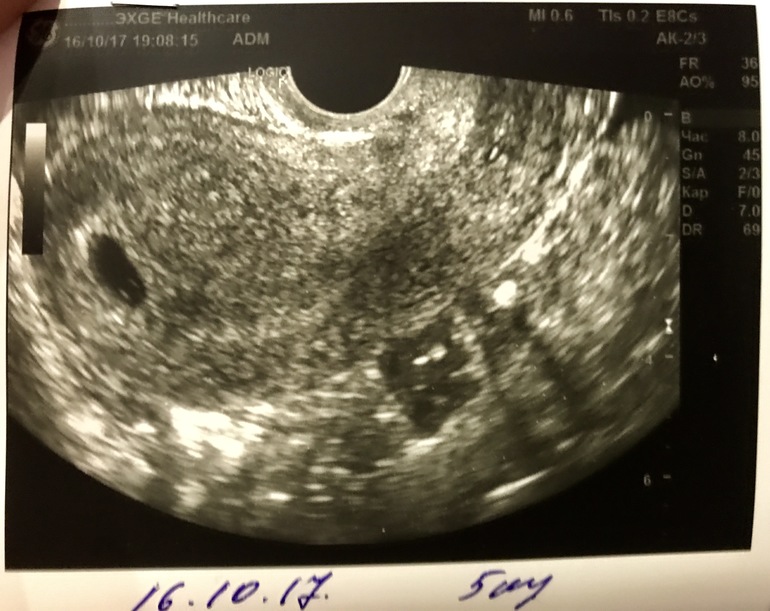

Вот мы и сходили на 1 УЗИ )) по менструации срок беременности 5 недель и 3 дня, пока эмбриона не видно, но сказали все ттт по срокам. Плодное яйцо 11 мм, желточный мешочек 3.5 мм, а у вас девчонки какие были показатели на таком сроке?

В 5 недель и 1 день, плодное яйцо 4,8 мм с эмбрионом, ктр 0,5 мм, желточный мешочек 0,9 мм